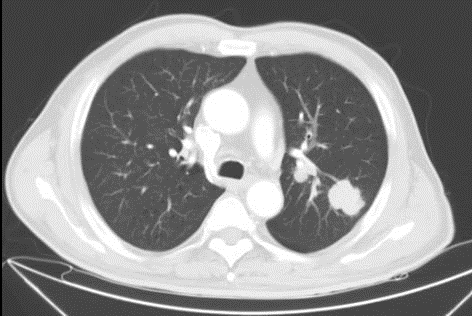

2022-08-08胸腹盆腔CT:1、左肺上叶占位并左肺门多发肿大淋巴结,考虑肺Ca并淋巴结转移,建议穿刺活检;双侧肾上腺占位,考虑转移瘤;腹膜后淋巴结转移2、双肺上叶磨玻璃小结节,较前变化不著;原左肺下叶实性小结节,现未见明确显示3、双肺肺气肿,多发肺大泡;双肺下叶少许炎症;左肺下叶钙化灶4、主动脉壁及冠状动脉壁钙化斑块5、右侧第5肋低密度影,建议随诊复查。

图2.首诊胸腹部CT

综合治疗1周期影像学报告(2022-09-07):结合病史,1、肺Ca复查,左肺上叶占位并左肺门多发肿大淋巴结,较前(2022-08-08)减小;双侧肾上腺占位,较前减小;腹膜后淋巴结转移,较前略减小;左侧颈部淋巴结转移,部分较前减小,请结合临床并复查。2、双肺肺气肿,多发肺大泡;双肺下叶少许炎症;左肺下叶钙化灶3、主动脉壁及冠状动脉壁钙化斑块。

综合治疗3周期影像学报告(2022-10-23):结合病史,肺Ca复查,左肺上叶占位,较前(2022.09.07)减小,左侧肺门淋巴结较前缩小;左侧肾上腺占位,较前减小;腹膜后小淋巴结,较前变化不著;左侧颈部淋巴结转移,较前减小。2、双肺肺气肿,多发肺大泡;双肺下叶少许炎症;左肺下叶钙化灶3、主动脉壁及冠状动脉壁钙化斑块。

综合治疗6周期影像学报告(2023-02-02):结合病史,肺Ca复查,左肺上叶占位,较前(2022.10.23)变化不著;左侧肺门淋巴结较前略缩小;左侧肾上腺占位,较前似略有减小;腹膜后小淋巴结,较前变化不著;左侧颈部淋巴结转移,较前减小2、双肺肺气肿,多发肺大泡;双肺下叶少许炎症;左肺下叶钙化灶3、主动脉壁及冠状动脉壁钙化斑块。

2023-03-18影像学报告:结合病史,肺Ca复查,左肺上叶占位,较前2023.02.02变化不著;左侧肺门淋巴结较前变化不著;左侧肾上腺占位,较前变化不著;腹膜后小淋巴结,较前变化不著;左侧颈部淋巴结转移,较前变化不著2、双肺上叶磨玻璃小结节,左肺下叶实性小结节,较前变化不著。3、主动脉壁及冠状动脉壁钙化斑块。

图4.治疗后胸腹部CT